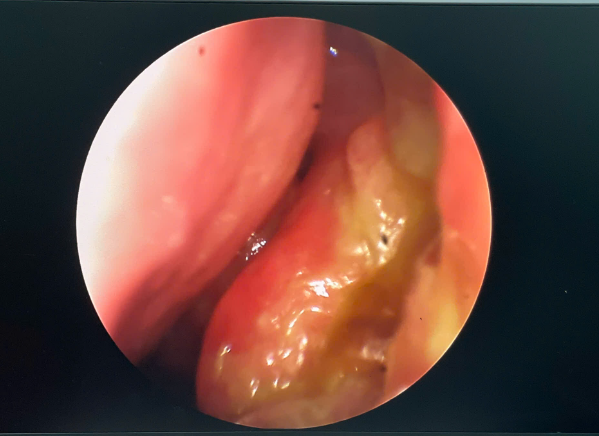

Hình 2. Hình ảnh túi lệ mũi được mở sau một tháng.

Kết quả sau phẫu thuật một tháng, bệnh nhân không còn xuất hiện tình trạng chảy nước mắt nhiều, không nghẹt mũi, hai hốc mũi thông thoáng

Sau phẫu thuật, tình trạng chảy nước mắt của bệnh nhân cải thiện rõ rệt. Khi bơm rửa lệ đạo, nước chảy xuống họng, không trào ra ở lỗ lệ trên và dưới, không xuất hiện nghẹt mũi. Hai hốc mũi được làm sạch và chăm sóc sau phẫu thuật thuận lợi.